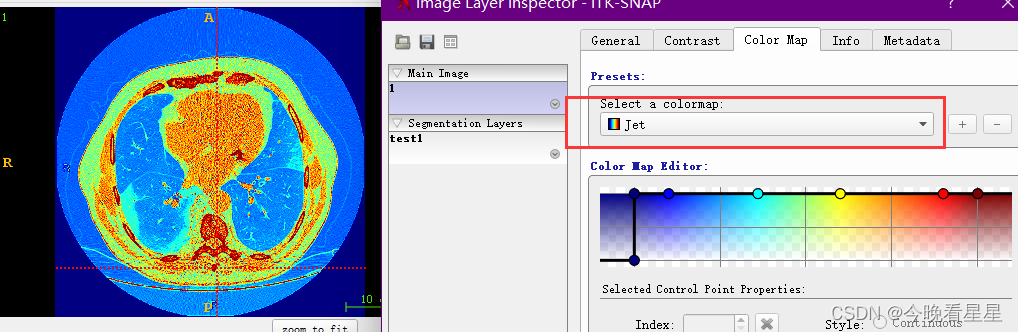

Contrast可用于调整窗宽窗位,主要是图像的对比度Color Map可用于调节显示的颜色,比如调节为伪彩,便于观察, 但常用的还是灰度图